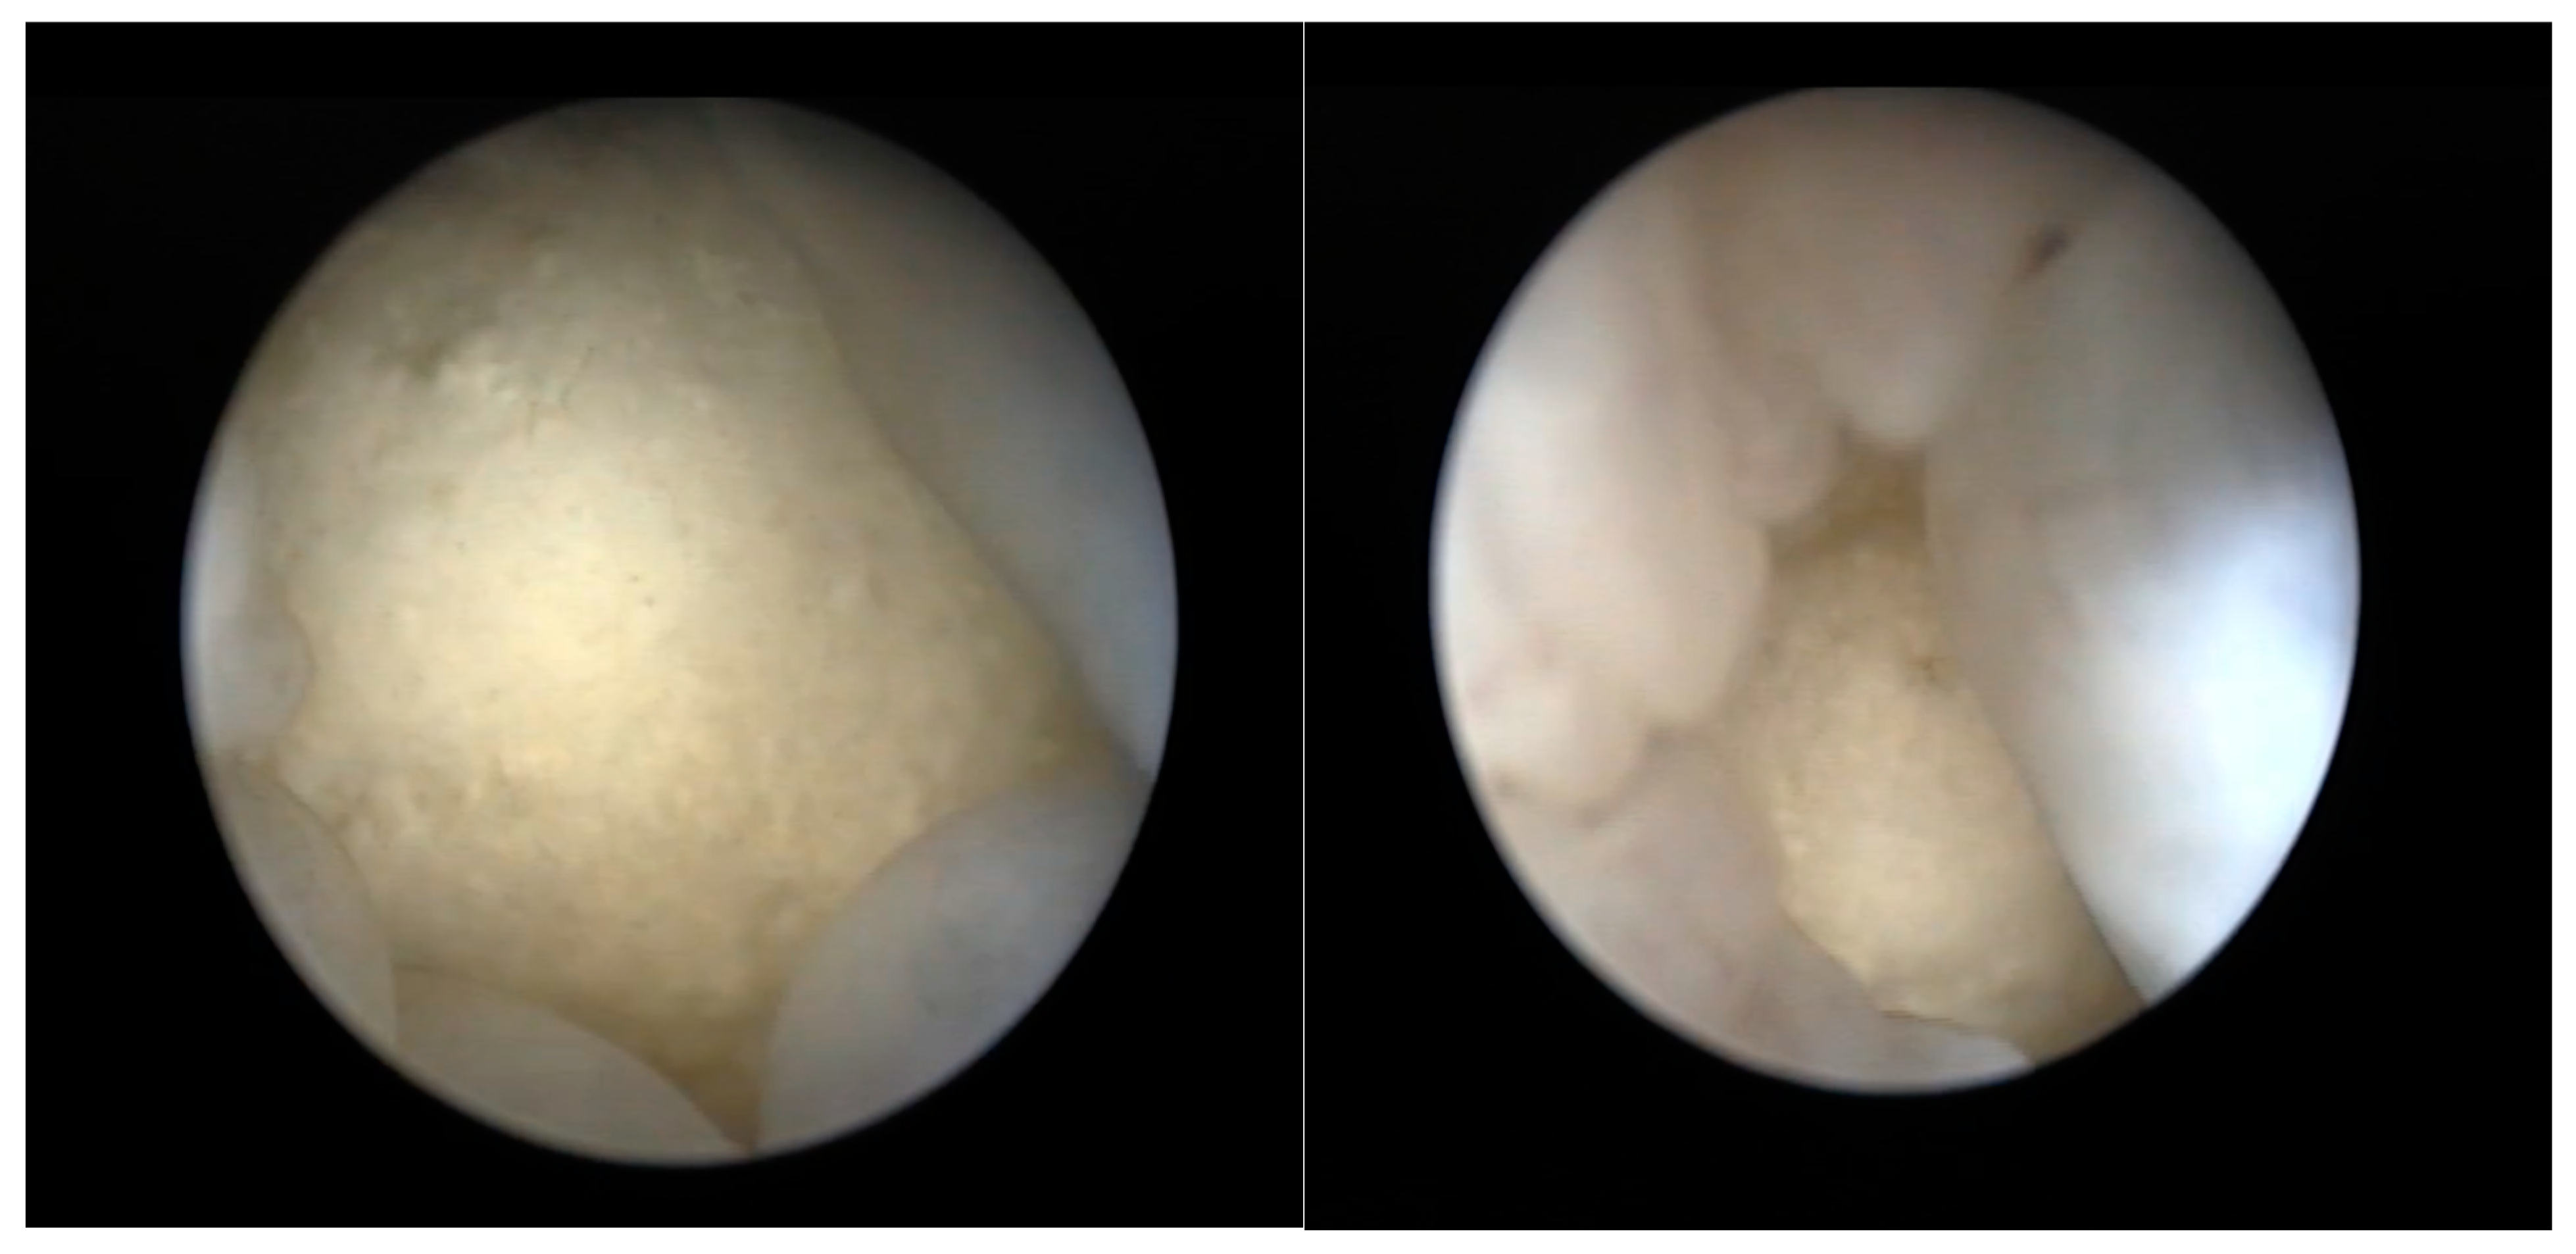

2.2.4. Coelioscopy

2.2.5. Cloacoscopy